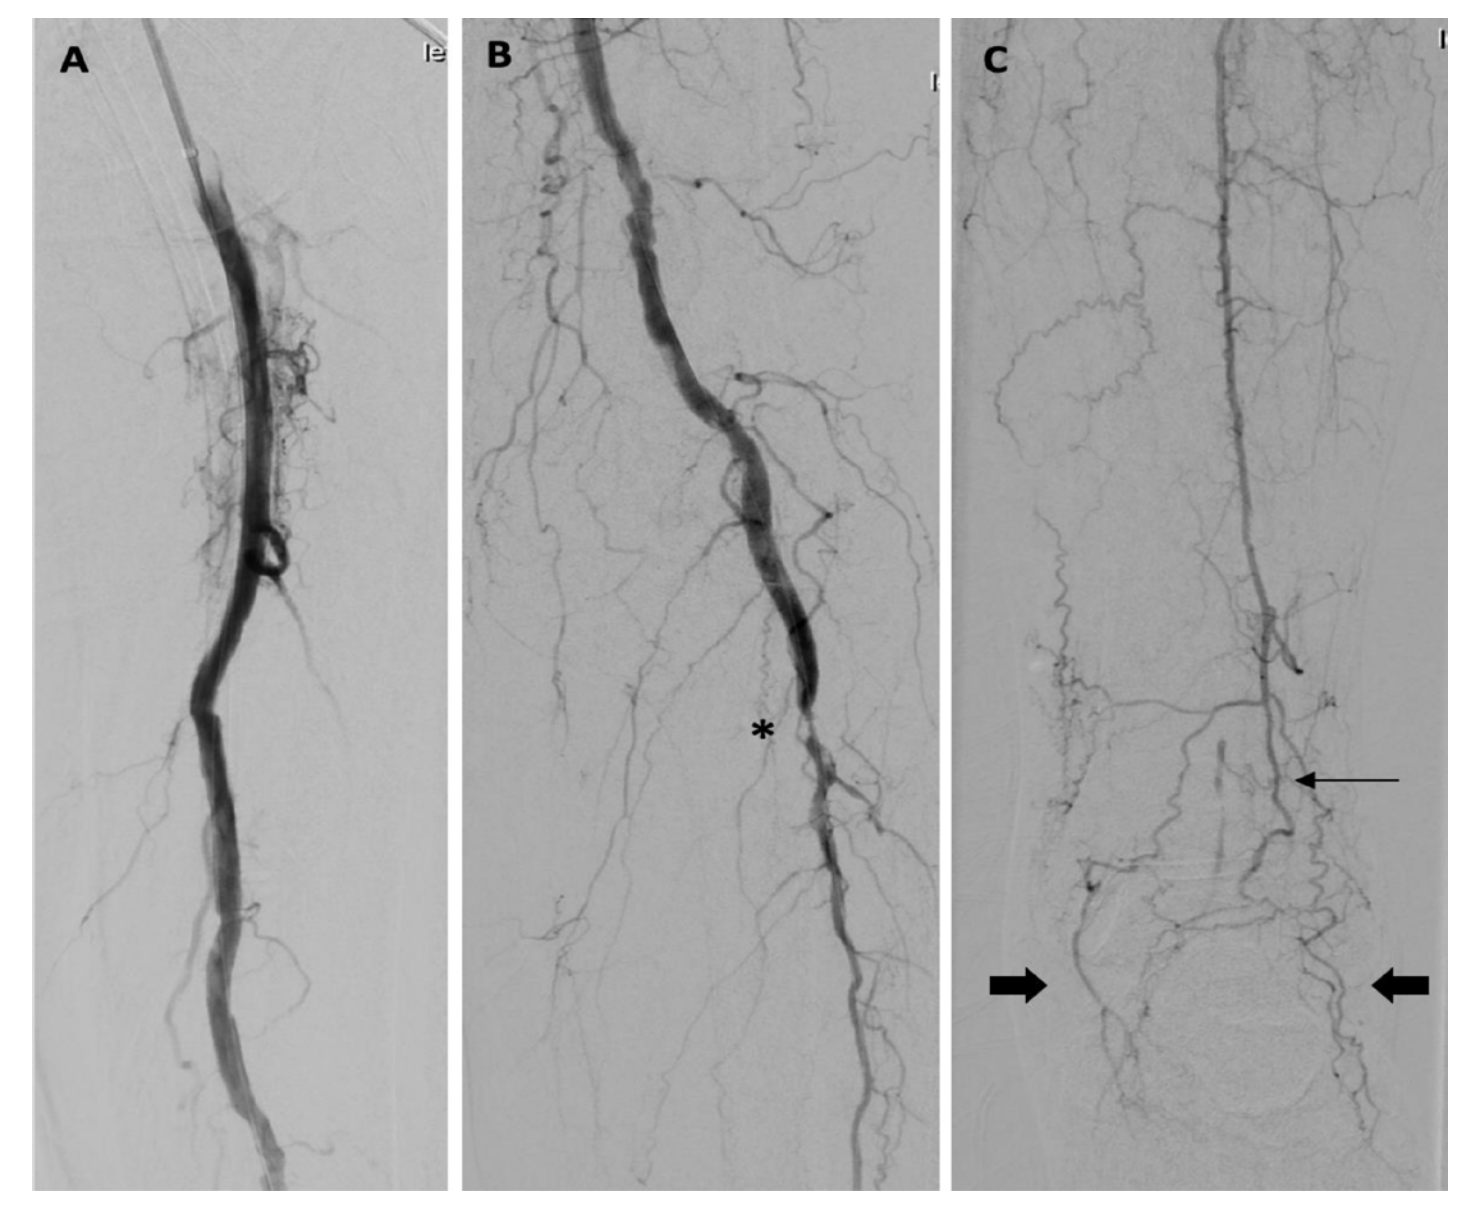

Acute Limb Ischemia Clot and Catheter VDM Catheter Blocked With Sediment Some of the signs the catheter might be blocked and may need flushing include: Bacteriuria or colonisation of the urine can develop as soon as 48 hours after the catheter is inserted. Blocked/ bypassing urethral catheter or spc causes: To review the literature showing that understanding how foley catheters become encrusted and blocked by crystalline bacterial. The use of catheter. Catheter Blocked With Sediment.